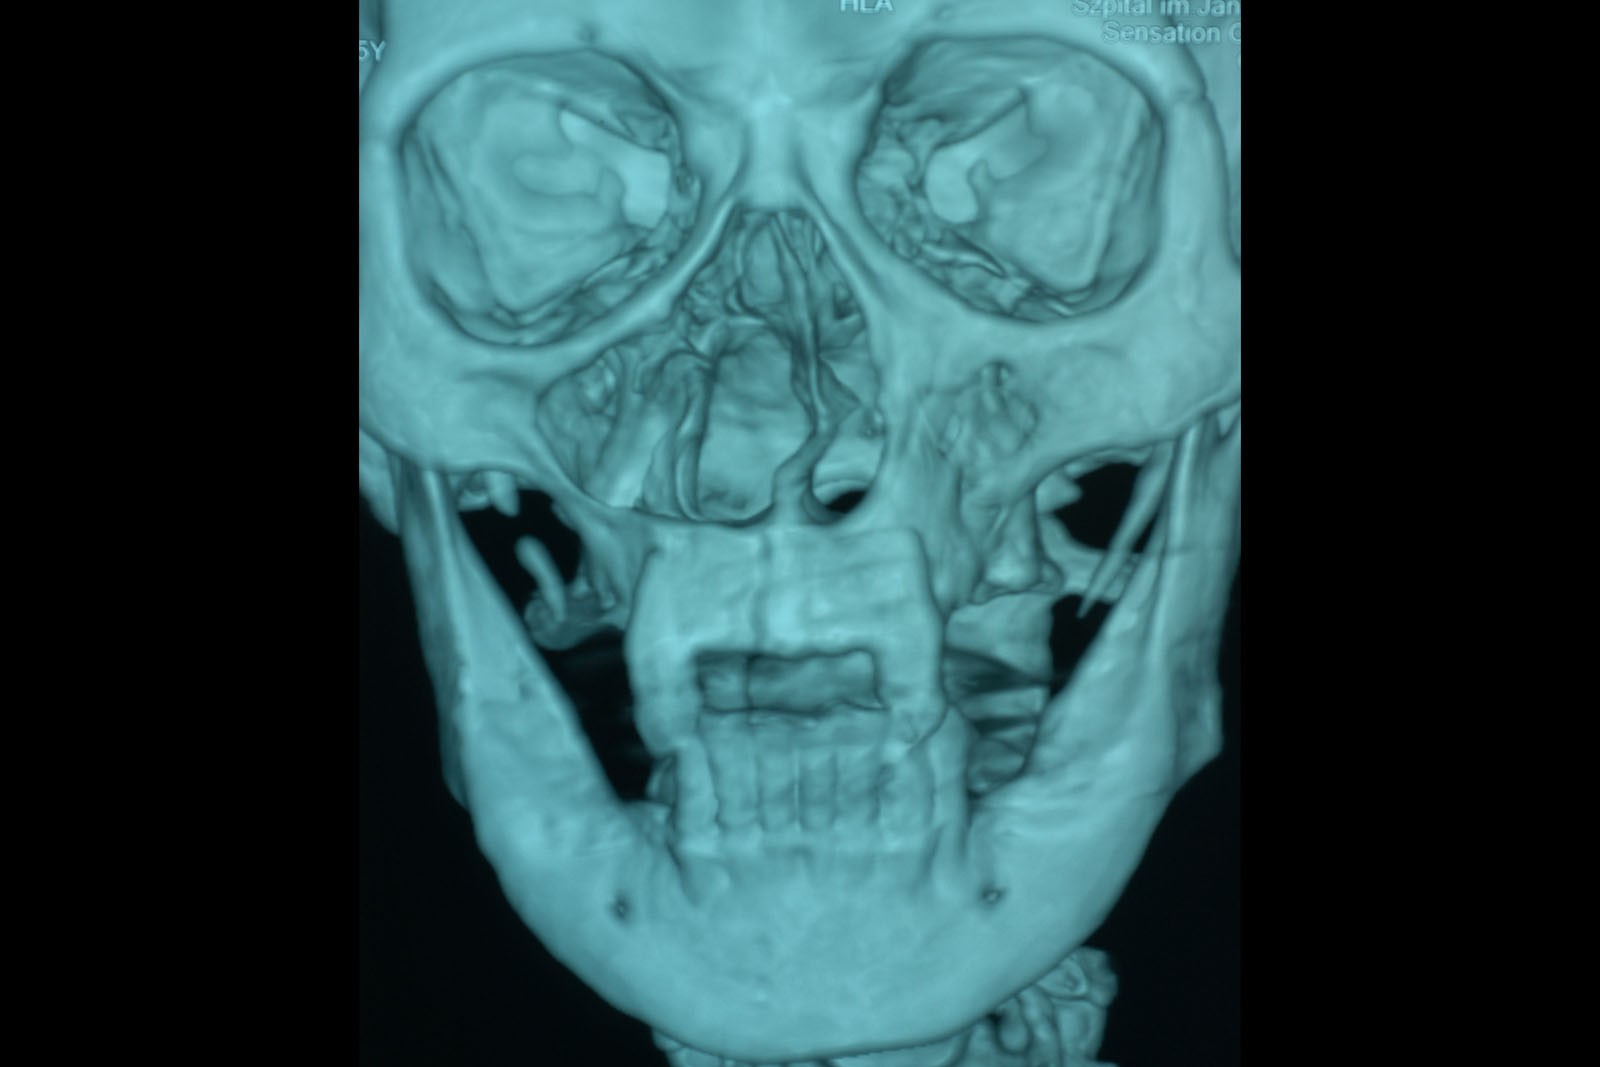

Chory po resekcji tkanek/narządów twarzoczaszki wymaga wnikliwej diagnostyki obrazującej zakres ubytku oraz stan podłoża kostnego. Wykonuje się zdjęcia radiologiczne RTG pantomograficzne szczęk OPG, konwencjonalną tomografię komputerową CT, stożkową tomografię komputerową CBCT, ukazującą trójwymiarowy obraz twarzoczaszki, oraz w razie potrzeby rezonans magnetyczny NMR. Możliwy jest również druk modeli 3D w skali 1:1 dowolnej części twarzoczaszki.

Diagnostyka ma za zadanie wykluczenie wznowy wyciętego nowotworu oraz pomoc w ocenie tkanki kostnej w okolicy ubytku. Ocena kości pozwala na zaplanowanie zabiegu wszczepienia implantów jako przyszłego fundamentu niezbędnego dla mocowania protez poresekcyjnych lub epitez twarzy.

Zastosowanie współczesnych technik obrazowania trójwymiarowego umożliwia precyzyjne zaplanowanie pozycji implantów czaszkowych, tak by ektoprotezę stabilnie osadzić na podłożu.